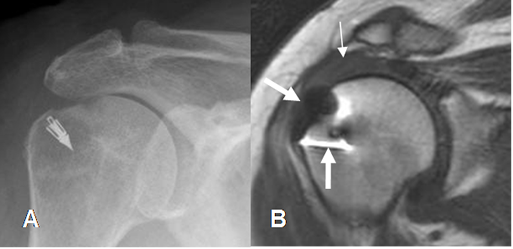

En el manguito reparado se aprecia irregularidad del tendón y señal baja o intermedia, por la cicatrización y fibrosis. (29). (Fig 159 y 160).

Fig 160. Cambios PostQx.

A: Rx AP. Material Qx por reconstrucción del manguito rotador.

B: RM coronal en T2. Reconstrucción de lesión del manguito, con un tendón del supraespinoso engrosado e hiperintenso, por tendinitis crónica. (Flecha delgada). Se aprecian artefactos metálicos. (Flecha gruesa).